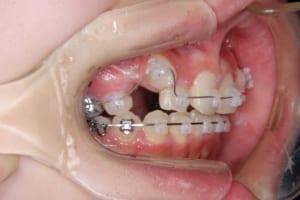

治療中

| 使用した装置 | 子どもの矯正治療(前期治療) 緩徐拡大装置 マルチブラケット装置 大人の矯正治療(後期治療/成人矯正治療) マルチブラケット装置 デーモンブラケット シルバーワイヤー 歯科矯正用アンカースクリュー(2本) ホールディングアーチ トランスパラタルアーチ |